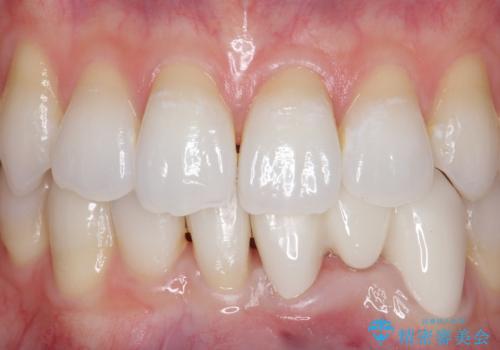

今回用いたオールセラミッククラウンはジルコニアフレームという白い素材の上にセラミックを盛っているため、審美性が非常に高いのが特徴です。

また、ジルコニアは人工ダイヤモンドの材料にも使われているほど高い強度を持っており、そのためオールセラミッククラウンは審美性だけでなく、奥歯やブリッジの補綴も可能とするクラウンです。